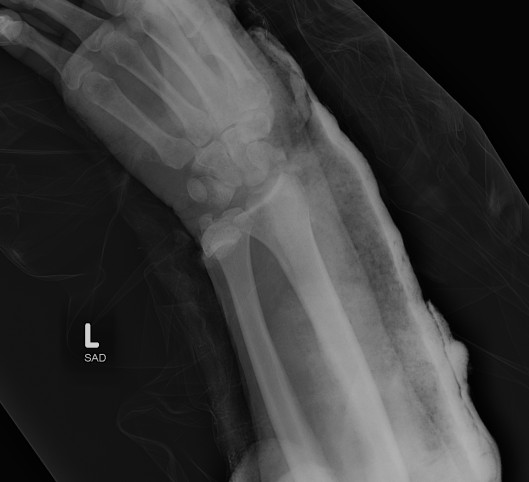

Dislocated Radiocarpal Joint Dislocated Radiocarpal Joint AP